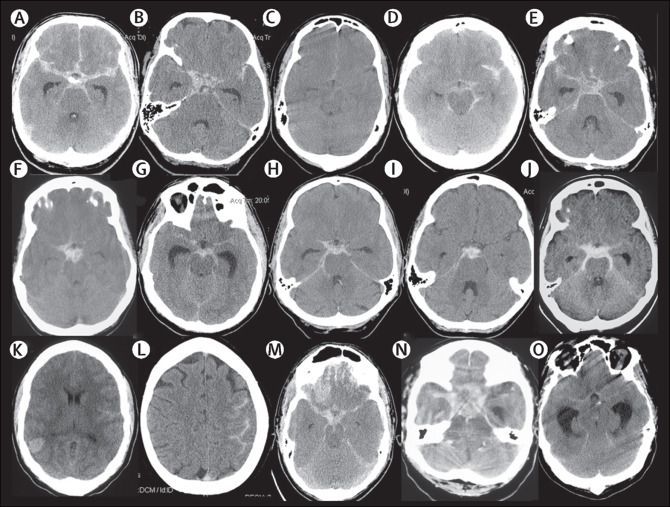

Subarachnoid hemorrhage refers to bleeding in the subarachnoid space. Patient may present with following signs and symptoms: - unconsciousness - diplopia - nausea - vomiting - severe headache - ptosis - dysphasia - stiff neck - seizures - photosensitivity - difficulty in concentrating - confusion' Reference: https://www.hopkinsmedicine.org/health/conditions-and-diseases/subarachnoid-hemorrhage Image via: https://www.thelancet.com/article/S0140-6736(16)30668-7/fulltext